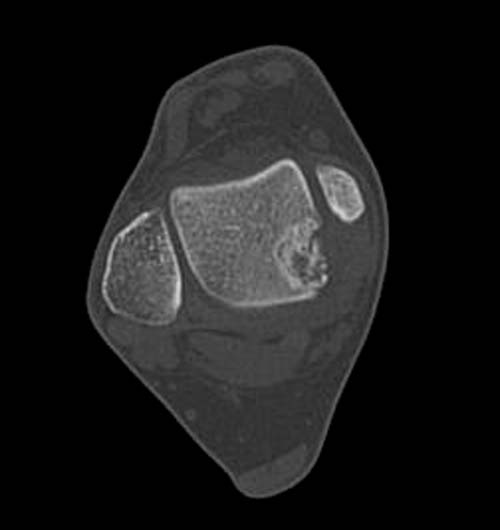

Разбираемый случай не имеет ничего общего с классическим Аваскулярным Некрозом Таранной кости. Здесь так назывемый (osteochondral defect) или osteochondritis dissecans (OCD) таранной кости, при котором патология локализуется в медиально-верхнем нагрузочном отделе. В основном OCD

встречается после хронической травмы, но бывают случаи врожденного генеза, которые обнаруживаются при случайных исследованиях.

Симптоматология  OCD выражается слабым отеком, а более сильные боли наступают после физической нагрузки. В отличие от АВН тарана, когда боли постоянные, а при OCD боли изчезают после отдыха. В начальных стадиях

на рентгенограммах не всегда заметны склерозные участки, и поэтому в большинстве диагноз устанавливается поздно. Приход КТ и МРТ улучшил диагностику, и в срезах внутри кисты можно увидеть жидкость, но это не означает проявление симптоматологии. Симптомы проявляются с момента образования внутрисуставных краевых фрагментаций!